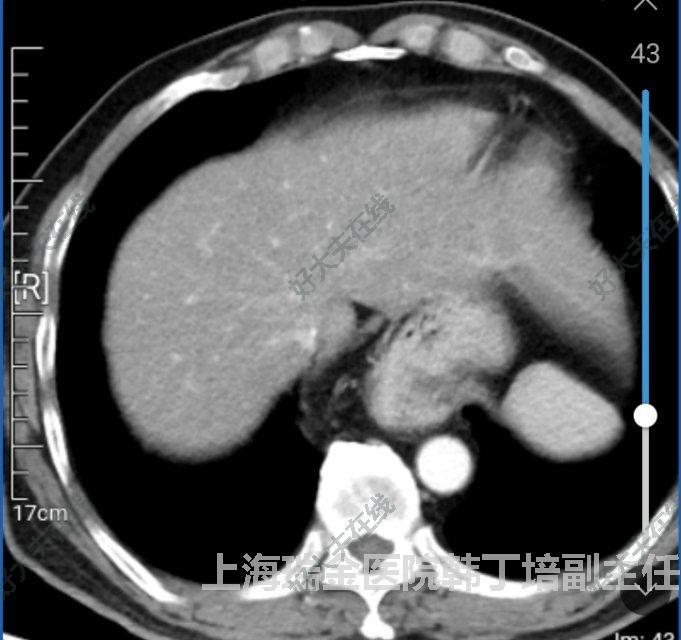

治療前老年患者,進食不適感數(shù)年,自知有食管裂孔疝,目前癥狀加重,進食流質(zhì)可,為要求手術就診。入院后ct提示部分胃底位于胸腔。完善各項檢查,擬行腹腔鏡微創(chuàng)食管裂孔疝修補+胃底折疊術治療中腹腔鏡探查見擴大食管裂孔,將胃拖回腹腔,游離賁門及食管下段,顯露兩側膈肌角,縫合后將食管裂孔縮小至正常大小。最后完成胃前壁胃底折疊。治療后治療后7天患者術后恢復好,正常進食后出院。總結:食管裂孔疝是老年高發(fā)良性疾病,通常內(nèi)科治療,癥狀加重,進食困難,有嵌頓風險時需要手術治療,首選微創(chuàng)手術。食管裂孔由左右兩側膈肌腳構成,松弛后形成裂孔疝,手術目的就是縫合兩側松弛膈肌腳,重建食管裂孔至正常大小。另外大多數(shù)患者有反流癥狀,所以需要做胃底折疊手術,根據(jù)癥狀輕重,折疊方式也有不同。老年患者手術指征需要嚴格把握。